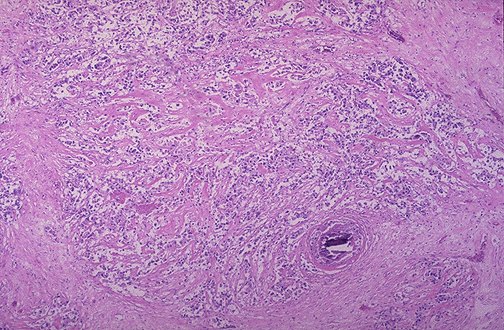

| This is infiltrating ductal carcinoma of breast. Note the infiltration of ill-defined glands into the surrounding collagenous stroma. There is also a small microcalcification at the lower right of center, a finding that could be seen by mammography. About 65 to 80% of breast cancers are of this type. |